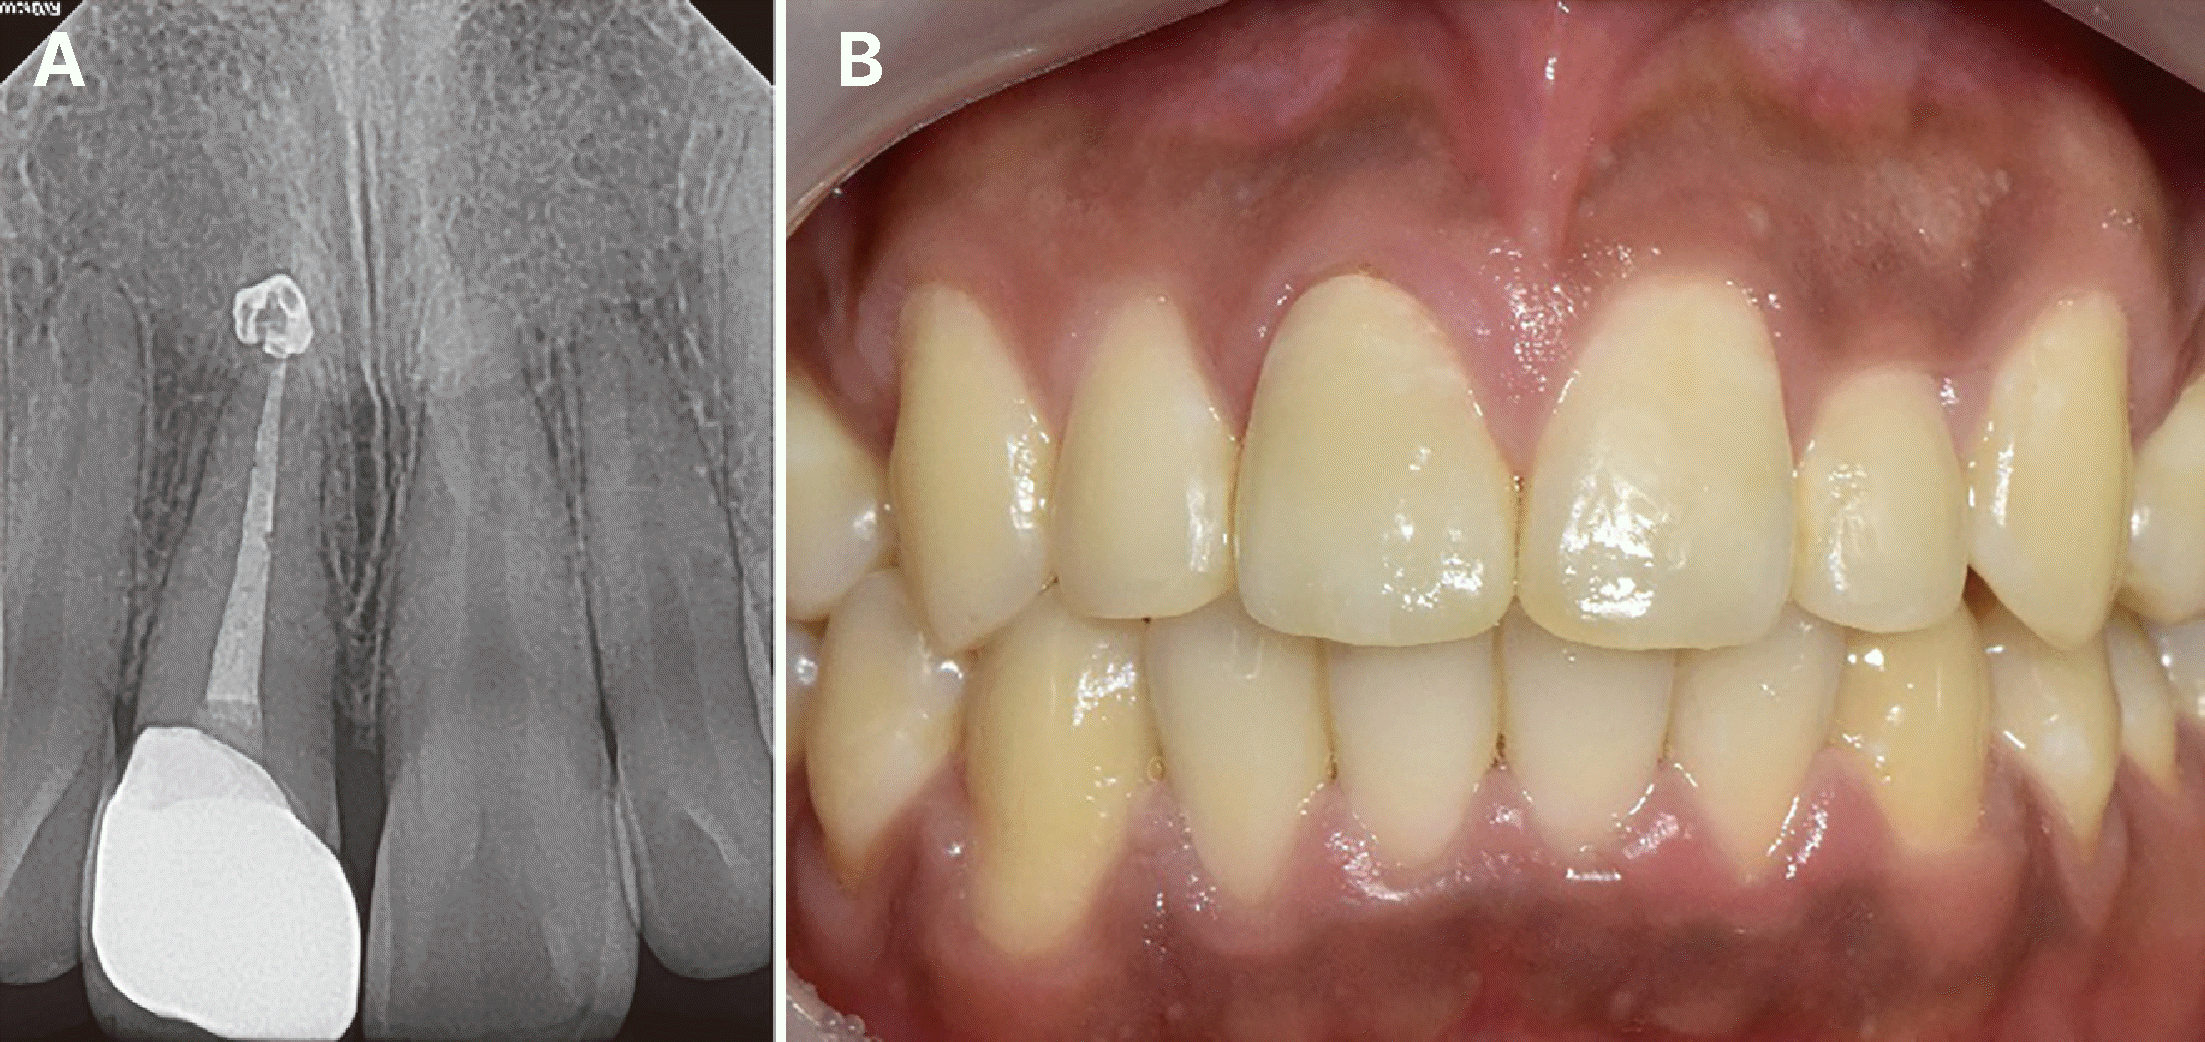

외과적 정출술을 시행하기 전 1 : 100,000 에피네프린이 함유된 2% 리도카인 한 앰플을 이용해 국소마취를 시행하였다. #15 blade를 이용해 치주인대를 절단하고 치은 섬유의 손상을 최소화하기 위해 젖은 멸균 거즈를 겸자와 치아 사이에 배치한 후 회전운동을 시행하여 치아의 동요도를 유도하였다. 치아를 치조와에서 완전히 분리하여 발거한 후 구개측 파절선의 경계를 확인하였으며 협측 치관부 중앙에서 관찰되었던 균열이 치근으로 연장되지는 않은 것 또한 확인할 수 있었다. 치아를 180°회전한 후, 구개측 파절선이 협측 치은연과 유사하게 위치되도록 재식 하였으며, 치축의 각도를 고려하되 치주인대에 압박이 가해지지 않도록 수동적으로 위치될 수 있도록 하였다. 정출은 2 - 3 mm 시행하였으며 수술에 소요된 총 구외시간은 5분 내외였다. 정출 후 스테인레스 스틸 와이어(TRU-CHROME® S.S., .016 × .022, Rocky Mountain Orthodontics, Denver, USA)를 사용하여 레진-강선 고정을 시행하였고 치아 양측 치은유두에 단순단속 봉합을 시행하였다(Fig. 2). 심미 목적으로 임시 수복했던 절단측의 레진과 구개측의 치질을 삭제하여 대합치와 교합되지 않도록 높이를 조정하였다. 환자는 유동식을 하도록 지시하였고 3일간 진통제와 항생제를 복용하도록 처방하였으며 2주간 클로르헥시딘으로 구강세척을 시행하였다.

Fig. 2

Surgical extrusion. (A) Photograph of extracted maxillary right central incisor, (B) Photograph of replanted maxillary right central incisor after 180° rotation. Temporary filling material is partially removed for resin wire splint procedure. Intraoral photograph, (C) Buccal view, (D) Palatal view.